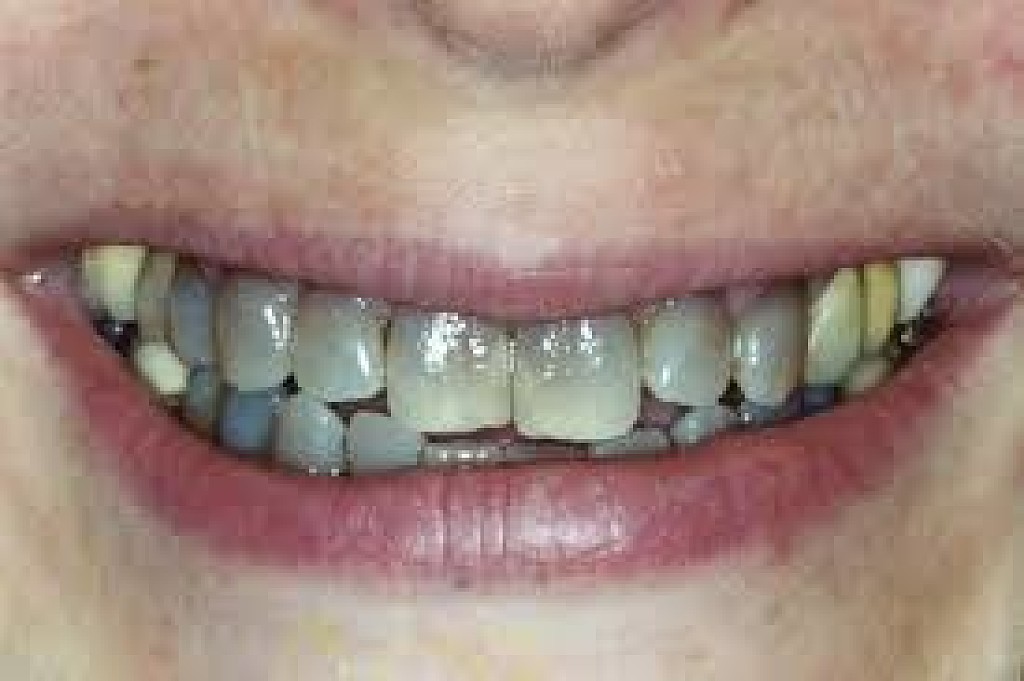

Poor oral hygiene

Poor oral hygiene can cause your tooth to go black. In the early stages this is likely to be staining from substances like tobacco, red wine and strongly colored food. If your oral hygiene routine is not thorough enough to remove the acid-excreting bacteria each day, the acid will slowly eat away at your tooth.

As the tooth gets eaten away, tooth decay sets in. Tooth decay naturally looks black and can give the appearance of a black tooth. This gives the look of rotten teeth and is a classic result of not looking after your teeth for a considerable period of time.

The death of a tooth

When a tooth dies, the blood supply – which gives the tooth its natural, healthy color – will stop. Because the tooth is not receiving the nutrients it needs, it will begin to necrotise, darken, die and slowly go black.

Will my tooth go black after root canal?

A common misconception is that a tooth will go black after a root canal treatment. Teeth will often go black before root canal treatment as the tooth rots and decomposes on the inside. If root canal treatment is done well, all of the decomposing tissue will be removed and the blackness will not get worse. There may, however, be some mild darkening of the tooth after a root canal, depending on exactly how the root canal treatment is done and with which material.

How long does it take for a tooth to go black?

If the cause of the blackness is due to tooth decay, the blackness can happen over a period of years. If the cause of the blackness is due to trauma, as soon as the blood supply has been cut off from the tooth, the internal tooth tissue will begin to die and turn black.

Will a dead tooth go black?

If a dead tooth is left untreated, it will go black as the internal tooth tissue dies and decomposes. If the dead tooth has been root treated with a tooth-colored treatment, the tooth may not go completely black, although it may darken slightly.